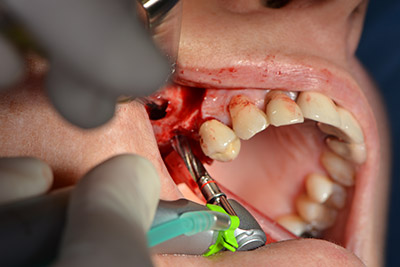

En el siguiente paso se efectúa la elevación del suelo del seno maxilar, a la vez que se coloca el implante. Para la fenestración lateral de la pared del seno maxilar Implantmed también cuenta con un ajuste predefinido en la primera posición.

La ventana se crea a una velocidad de 35.000 rpm y, a continuación, la membrana de Schneider se prepara en sentido craneal (figuras 13 a 14).